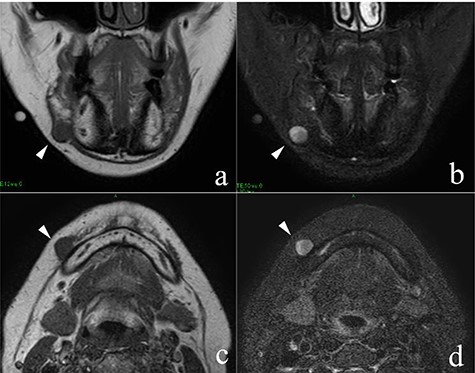

MRI findings; the arrowheads indicate the schwannoma; (a) low signal intensity on T1-weighted coronal image; (b) high signal intensity on T2-weighted coronal image; (c) low signal intensity on T1-weighted axial image; (d) high signal intensity on T2-weighted axial image.

She had a 15-mm, painless, non-pitting and indurated mass at the right mandibular margin (Fig. 1). Oral examination revealed no mucosal abnormalities or swelling. The mass was difficult to palpate from the oral side due to the presence of buccal frenulum on the mucosa over the mass. Magnetic resonance imaging (MRI) revealed a 15-mm nodule with a clear border at the right mandibular margin, with low and high signal intensities on T1- and T2-weighted images, respectively (Fig. 2). Computed tomography (CT) revealed a 15-mm low-density nodule in the right mandibular margin. Calcification, bone invasion or lymph node enlargement were not observed (Fig. 3). The mass was radiologically diagnosed as an epidermoid cyst. The differential diagnoses were schwannoma, neurofibromatosis, pleomorphic adenoma and a powdery mass; however, schwannoma was considered to be most likely.